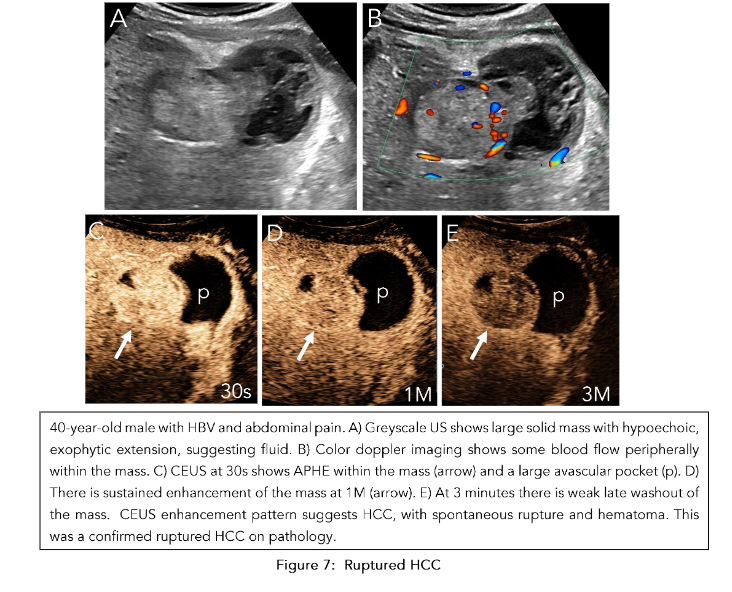

Our validated provincial protocol uses CEUS as the first test to characterize focal liver lesions, with many not requiring MRI prior to management planning. In a prospective study of 195 at-risk patients receiving routine surveillance with greyscale US, CEUS LI-RADS categorization demonstrated equal if not superior efficacy to MRI in diagnosing HCC when used as a first-line test following positive surveillance ultrasound. Moreover, when we maintain ultrasound as the foundational imaging mechanism for both surveillance and nodule characterization, we can achieve better correlation of surveillance findings with CEUS than MRI. When it concerns sub-centimeter nodules flagged on surveillance for further characterization, CEUS also excels in characterizing the enhancement and washout properties given its high spatial resolution and purely intravascular contrast agent. In the event a sub-centimeter nodule demonstrates APHE and late and weak washout, it is categorized as LI-RADS 4, but individual discretion dictates whether a short interval follow-up (less than 3 months) or immediate treatment is appropriate. CEUS also plays an important role when evaluating complications such as HCC rupture (Figure 7). Outside of following up positive surveillance findings, CEUS plays an important role in clarifying indeterminate findings on CT or MRI. In a prospective study of 27 indeterminate hepatic nodules characterized on CT, CEUS was able to accurately diagnose HCC in 7 cases. CEUS and MRI are also able to comparatively supplement each other in cases where there is no definitive diagnosis of HCC. Overall, a complementary framework where these imaging modalities are used in a multidisciplinary approach to HCC diagnosis is critical when forming management strategies.

The observations in the secondary surveillance period follow the CEUS LI-RADS treatment response algorithm (TRA). In a technically adequate exam, the ablation site is assessed for both intralesional and perilesional tumor viability.

If there is no enhancement within the ablation bed, it indicates the absence of a viable tumor. Uncertain viability is characterized by arterial phase hypoenhancement (with or without washout), while hyperenhancement or isoenhancement (with or without washout) suggests the presence of a viable tumor (Figure 10). -

Absent viability is characterized by homogeneous enhancement of the ablation margins compared to the rest of the liver. Uncertain viability is characterized by arterial phase hyperenhancement without washout, isoenhancement with washout, or hypoenhancement. The presence of a viable tumor is confirmed by hyperenhancement with washout (Figure 11). Once both these categories are assessed, an overall treatment response score is determined based on their respective contributions:

Only when there is absent viability in both intralesional and perilesional viability is the final category designated as LR-TR nonviable (Figure 12).